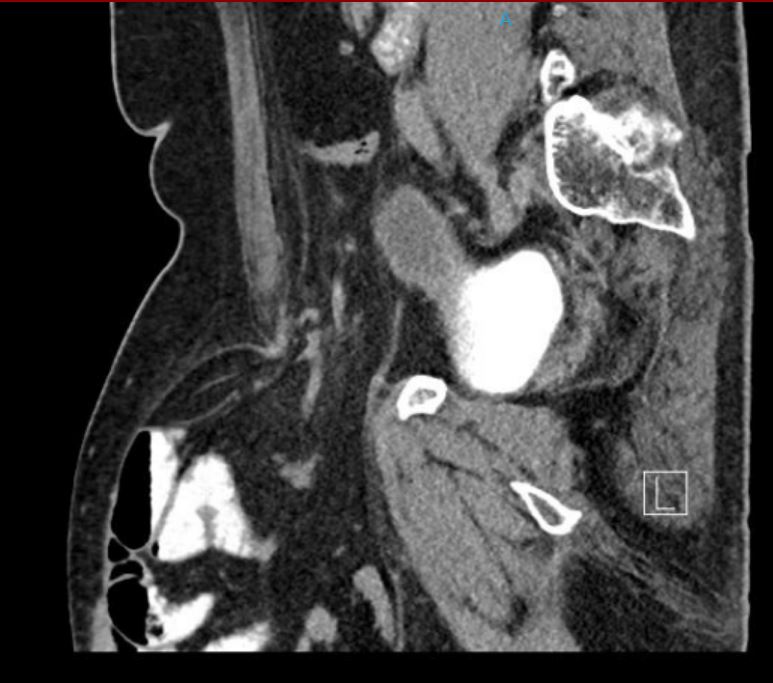

Methodik: Externe Vorstellung des Patienten mit Meläna und vorliegen einer komplexen anatomischen Ausgangssituation bei Zustand nach pyloruserhaltender Pankreaskopfresektion mit Teilresektion der Pfortader aufgrund chronischer Pankreatitis. Zusätzlich besteht eine Pfortaderthrombose mit konsekutivem portalen Hypertonus. In der extern durchgeführten Gastroskopie zeigte sich frisches Blut in den Dünndarmschlingen sowie Ösophagusvarizen Grad III. In der durchgeführten Computertromographie (CT) konnte keine aktive Blutung nachgewiesen werden, jedoch bestanden ausgeprägte portosystemische Kollateralen. Es erfolgte die Übernahme in die Universitätsmedizin Göttingen. Hier erfolgte eine transhepatische Stentimplantation der Vena portae nach erfolgreicher transhepatischer Rekanalisation. Im weiteren Verlauf zeigte sich jedoch in der CT-Untersuchung eine In-Stent-Thrombose, woraufhin eine erneute, jedoch frustrane Rekanalisationsmaßnahme durchgeführt wurde. Entscheidung zur endoskopischen Intervention.

Ergebnis: Die Hepatikojejunostomie konnte erfolgreich endoskopisch dargestellt werden. Es zeigten sich mehrere ausgeprägte Gefäßkonvolute im Sinne von Varizen. Nach gezielter Punktion einer Varize erfolgte die Applikation von drei mit Faser versehenen Coils (je 7 mm). Zusätzlich wurde eine Portion Histoacryl injiziert. Im Anschluss wurde eine weitere Varize punktiert und mit zwei Coils (8 mm, ohne Faser) sowie zwei Portionen Histoacryl versorgt. Endosonographisch zeigte sich im Farbdoppler ein sehr gutes Akutergebnis. Endoskopisch traten keine akuten Komplikationen auf.

Abbilung 1: Endoskopisches Bild der Ösophagusvarizen (A) und der Varizen im Bereich der Hepatikojejunostomie (B)

Abbildung 3: (A) Preinterventionelle transkutane Sonographie mit Darstellung der Varizen, (B) Postinterventionelle transkutane Sonographie